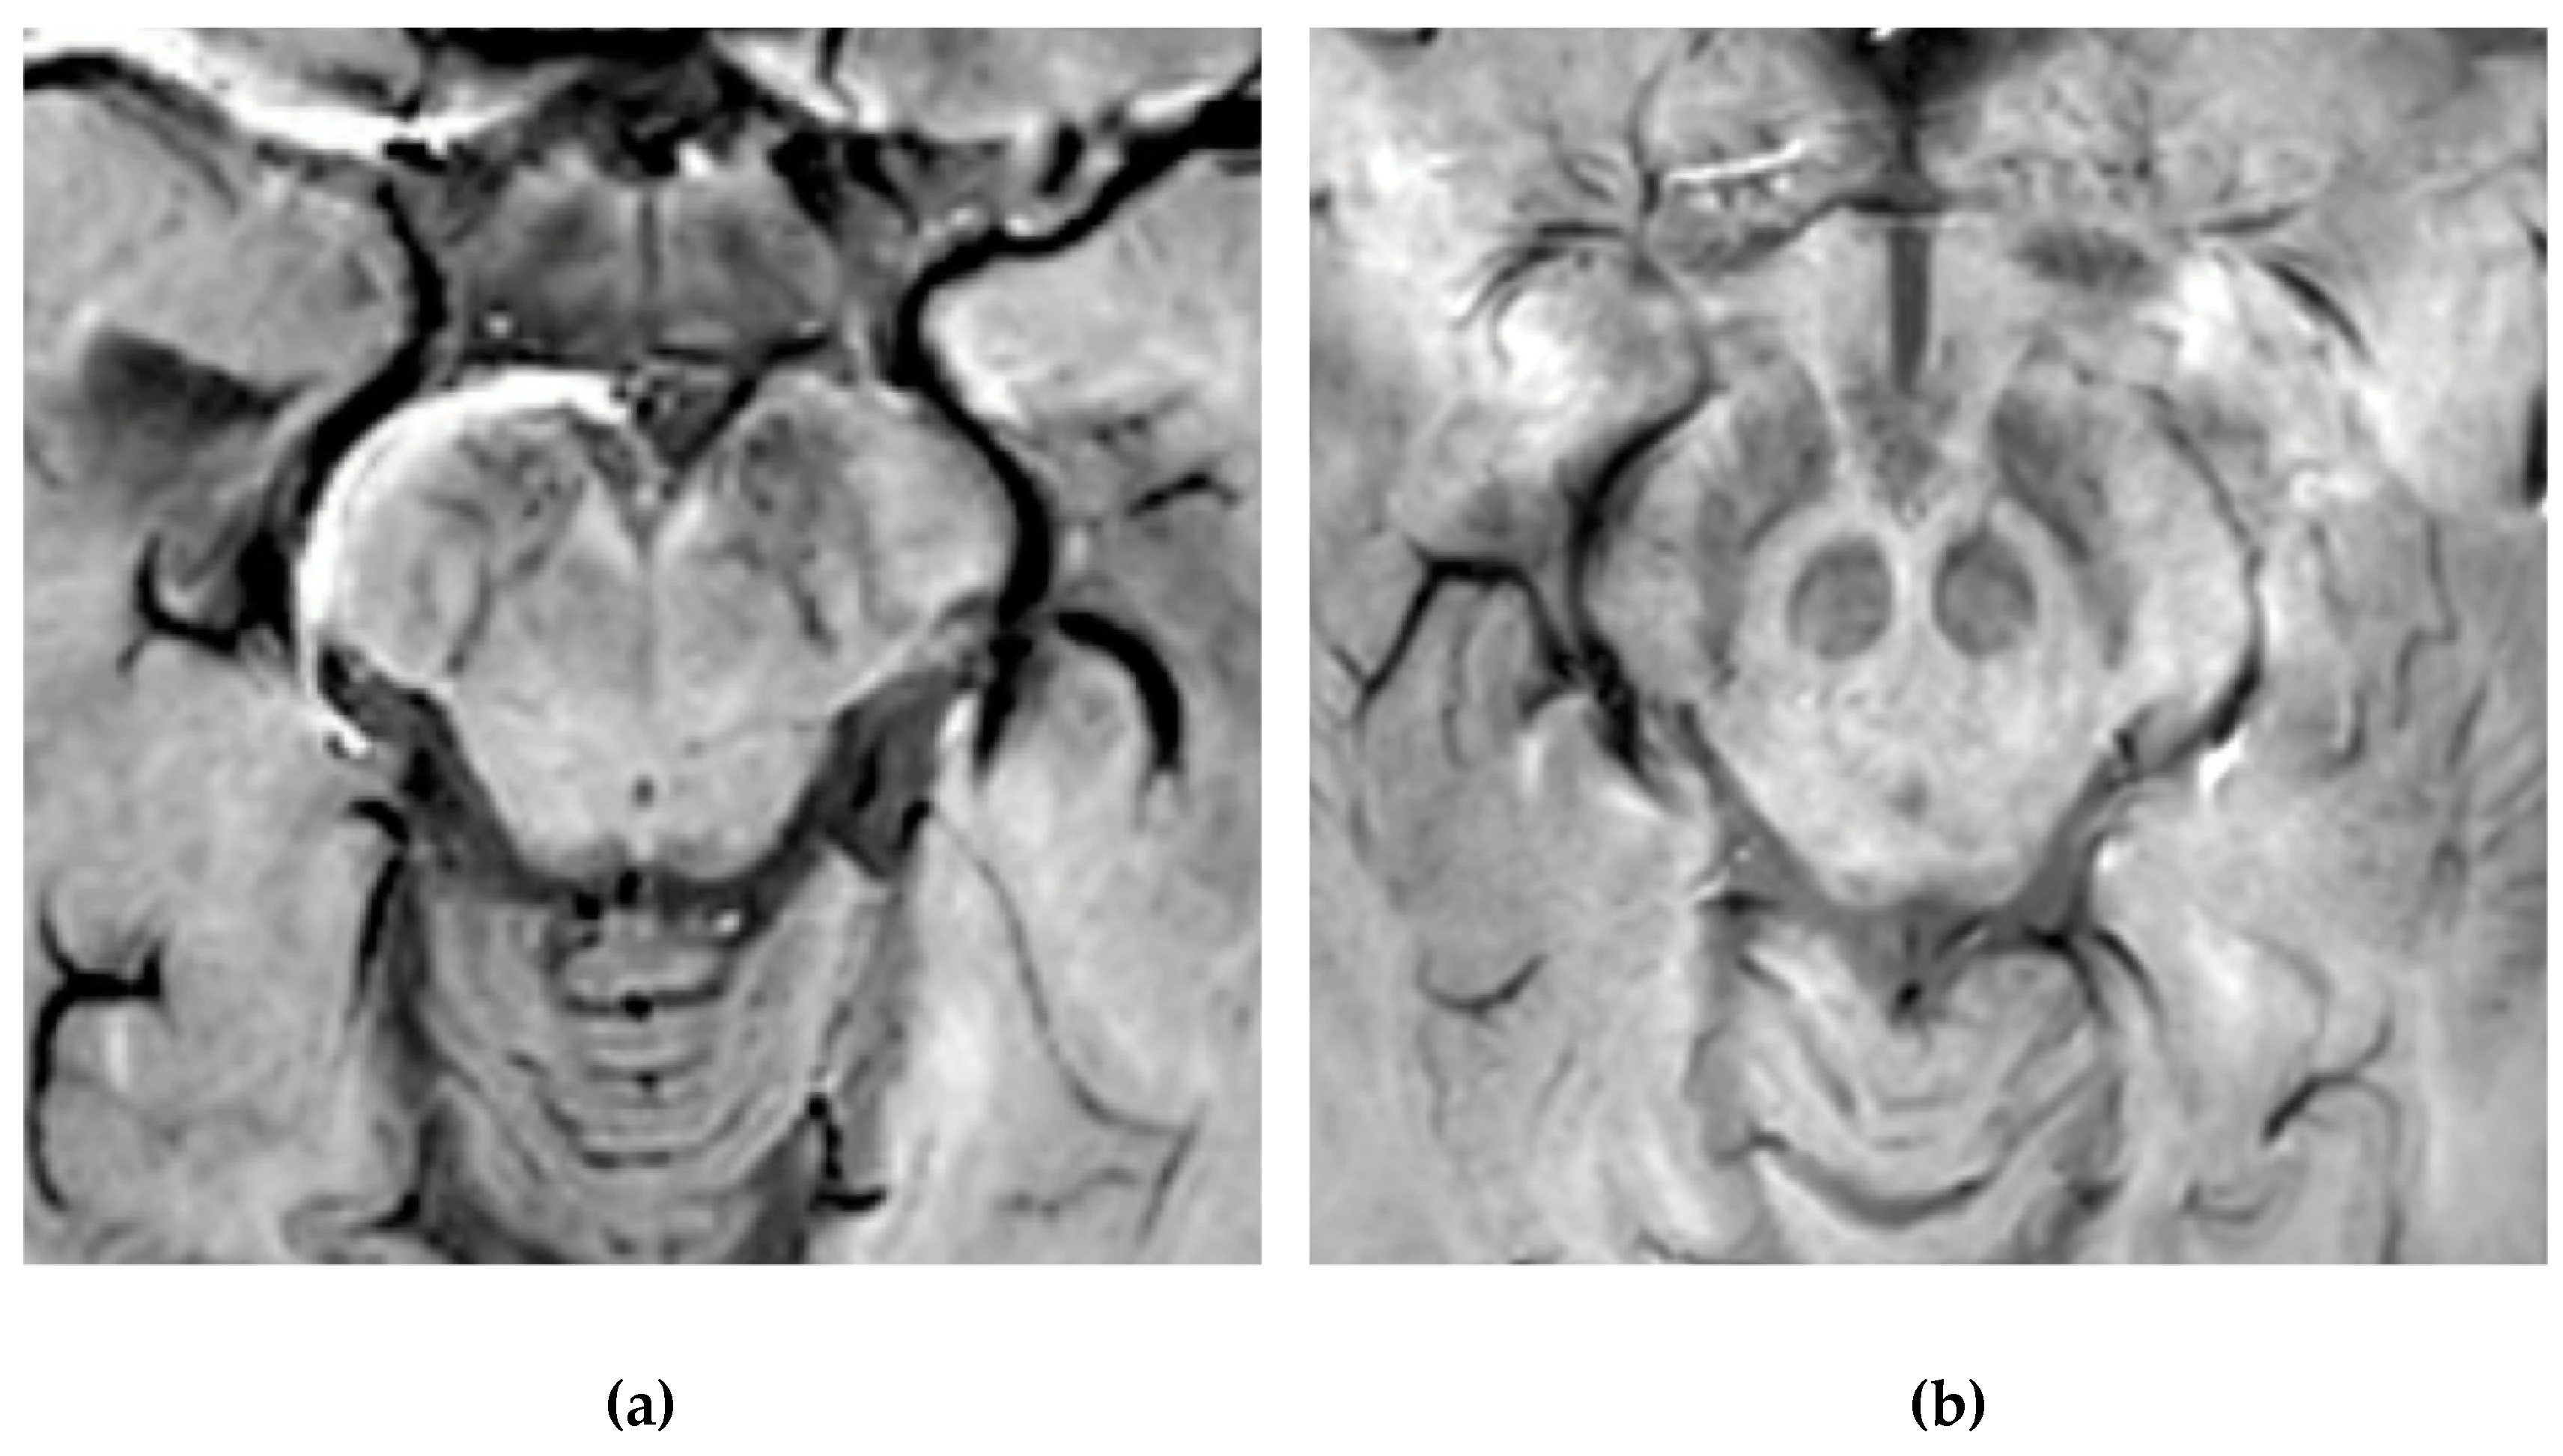

Normal nigrosome-1 and the surrounding structure of the dorsolateral SN appear as a swallow tail [40], and they can be visualized in 95% of healthy subjects [41,42]. Iron deposits and microvessels have been reported as contributing to the hyposignal surrounding nigrosome-1 in the SWI of normal aged midbrains [43]. Nigrosome-1 in PD patients displays a significant loss of STS on T2* weighted images, probably due to a reduction in NM within dopaminergic neurons, an increase in free iron (which induces local inhomogeneity in the magnetic field resulting in signal loss), or a loss of paramagnetic NM–iron complexes [44,45]. As the disease advances, a loss of T2* hyperintensity in PD has been demonstrated to progress from nigrosome-1 to nigrosome-4 [46]. The absence of STS may assist in the differential diagnosis for PD if compared with controls and ET, ultimately reaching high sensitivity and specificity [17,40,47,48] (Figure 4).

Figure 4.

Susceptibility-weighted imaging (SWI) scan performed with a 3T MR. (a) Presence of regular swallow tail sign in a healthy patient; (b) loss of swallow tail sign in a patient with Parkinson’s disease.

Moreover, the imaging of nigrosome-1 with 3T MR has been demonstrated to differentiate drug-induced Parkinsonism from idiopathic PD with elevated accuracy, thereby being of assistance in screening patients who required dopamine transporter imaging [49]. Furthermore, a loss of STS has also been observed in patients suffering from idiopathic rapid eye movement sleep behavior disorder and DLB [50,51]. Whilst the loss of nigrosome-1 on SWI sequences may assist as a potential imaging biomarker in the diagnosis of degenerative parkinsonian syndromes, it cannot differentiate between idiopathic PD and PS [52,53]. Nevertheless, it has been reported that anatomical changes of SN, detected via the SWI sequence at 7T, may distinguish MSA and PSP from CBD [54], thereby confirming the pathological heterogeneity of these diseases. Of note, nigrosome-1 has also been visualized on 3D FLAIR images as an hyperintense structure within otherwise surrounding hypointense dorsolateral SN. Its loss can be used to predict presynaptic dopaminergic function and to diagnose PD with a high degree of accuracy [55].